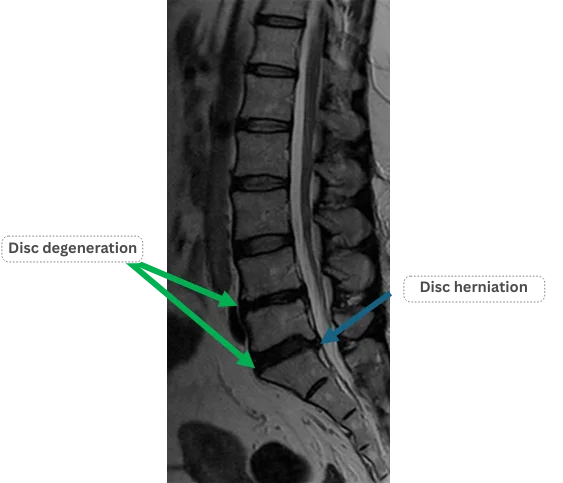

Imaging and findings

L1/2: No abnormalities

L2/3: No abnormalities

L3/4: No abnormalities

L4/5: Disc degeneration

L5/S: Disc degeneration, disc herniation

The above findings were also observed on the imaging.

Degeneration and herniation at L4/5 and L5/S are considered the most likely causes of the patient’s primary symptoms.